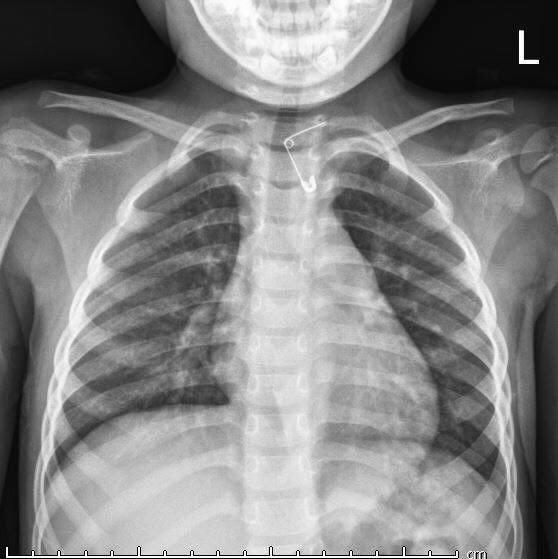

(PLVN) -Ngày 15/3, các Bác sĩ Khoa Khám bệnh, Bệnh viện Sản Nhi Quảng Ninh vừa nội soi gắp thành công chiếc kim băng trong thực quản cho bé Vũ Thu N.(04 tuổi), thường trú tại Cẩm Phả tỉnh Quảng Ninh.

Kết quả khám lâm sàng cho thấy hình ảnh dị vật là một chiếc kim băng đang mở, một đầu nhọn đang cắm vào thành thực quản của trẻ.